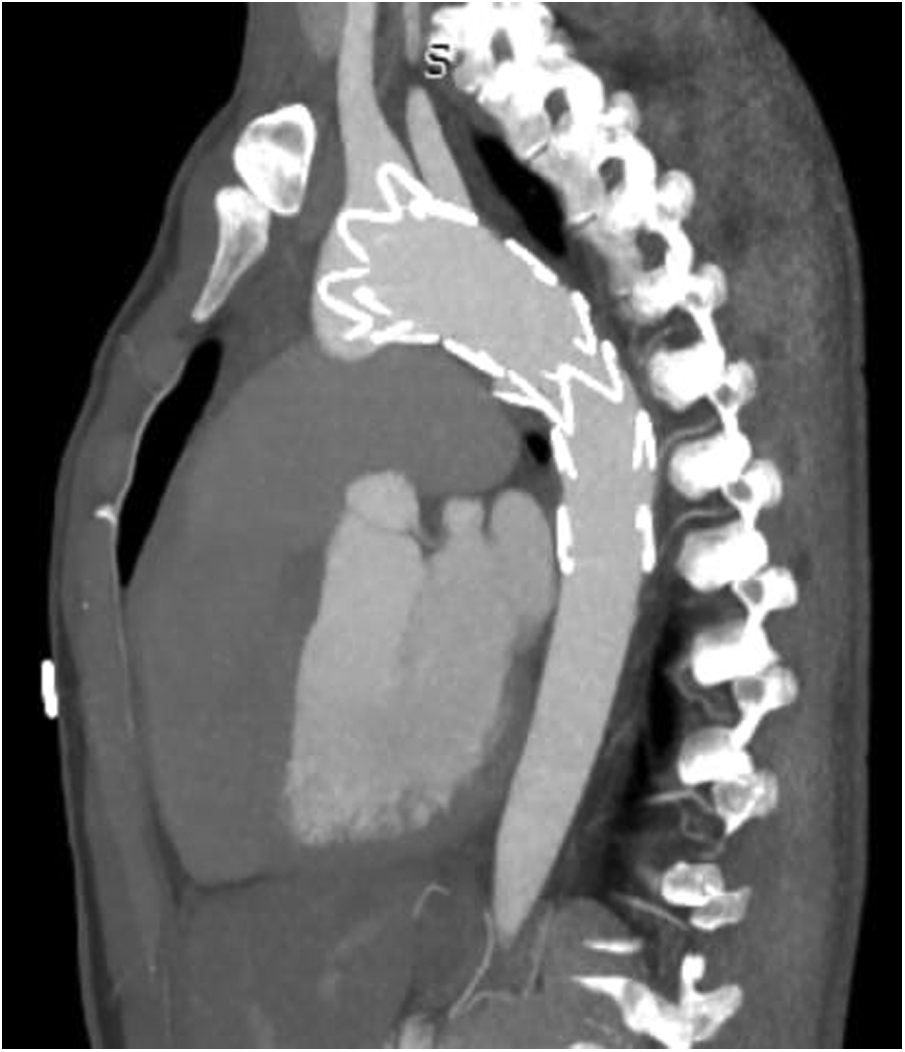

TEVAR was performed while the patient was under conscious sedation, using the pre-close technique with 2 Proglide devices. Custom-made Zenith Alpha Thoracic Endovascular Graft (44 26 128 mm, Cook Medical, Bloomington, IN, USA) was inserted through the right common iliac artery. The patient underwent a zone 2 deployment of a TEVAR graft with the coverage of the LSA. Echocardiography and aortography after TEVAR showed complete closure of PDA without any endoleaks (Figure 2). The post-surgical period was uneventful, and the patient was discharged two days after the procedure with no major complications, taking interpulmonary hypertensive drugs. One month after TEVAR, CT angiography was performed that revealed complete occlusion of PDA with no endoleaks (Figure 3). Due to residual pulmonary hypertension, echocardiography is being performed annually. A detailed, comprehensive timeline of the patient's clinical course is provided in Table 1.

Figure 3. CT angiography after one month showed no endoleak with complete occlusion of PDA shunt. CT, computed tomography; PDA, patent ductus arteriosus.